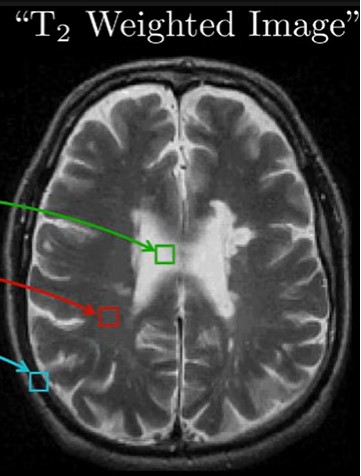

what is a T2 weighted image?

based on imaging using echo times, the voxel tells us how quickly the precessing spins in the voxel got out of phase with each other

bright if they dephase slowly

dark if they dephase quickly

<p>based on imaging using echo times, the voxel tells us how quickly the precessing spins in the voxel got out of phase with each other</p><p>bright if they dephase slowly</p><p>dark if they dephase quickly</p>

what is echo time?

how long you wait to detect signal once spins have been knocked out of alignment with field/excited

parameter chosen by MRI technician deliberately to maximise contrast between tissues of interest

at certain echo time, tissue has different signal strength, corresponding to different brightness of tissue

<p>how long you wait to detect signal once spins have been knocked out of alignment with field/excited</p><p>parameter chosen by MRI technician deliberately to maximise contrast between tissues of interest</p><p>at certain echo time, tissue has different signal strength, corresponding to different brightness of tissue</p>